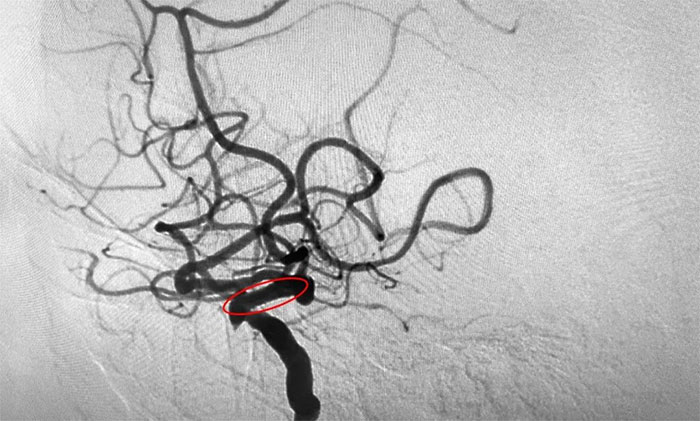

为进一步明确诊断并制定治疗方案,周君主任与医院学术副院长兼神经内科4A病区主任席刚明教授对患者病情开展了讨论评估,由席教授为患者进行DSA全脑血管造影检查,造影可见左颈内动脉岩骨水平段中度狭窄,左颈内动脉海绵窦段轻度狭窄,左颈内动脉眼动脉重度狭窄(狭窄程度约高于80%)。

▲ DSA检查影像